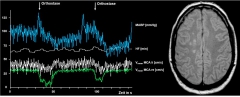

Die hochspezialisierte Ultraschalldiagnostik der neurovaskulären Spezialambulanz geht weit über die Graduierung und ätiologische Einordung von Gefäßerkrankungen hinaus. Die Beurteilung der individuellen thrombogenen und emboligenen Vulnerabilität eines stenosierenden Gefäßprozesses sowie dessen zerebral-hämodynamische Relevanz erlaubt es uns, die wahrscheinliche Pathophysiologie eines drohenden Schlaganfalls zu erkennen, dessen Risiko semiquantitativ abzuschätzen und die Prävention bzw. Therapieempfehlung individuell darauf auszurichten (Abbildung 3).